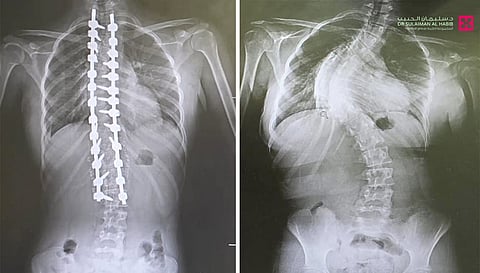

حيث جاءت المراجعة إلى المستشفى وهي تشتكي من تحدب وإنحاء جانبي، وآلام حادة ومزمنة في الظهر، وغيرها من الأعراض التي تسببت مجتمعة في الحد من حركتها، وقدرتها على ممارستها حياتها بشكل طبيعي، وعقب وصولها إلى المستشفى تم إخضاعها للفحوصات المخبرية وأشعة الرنين المغناطيسي Mri والأشعة السينية X- ray لكامل منطقة الظهر، حيث أكدت النتائج وجود انحراف مزدوج وحاد بزاوية "95" درجة، وأخضعها الفريق الطبي لعملية جراحية، تم فيها تقويم العمود الفقري باستخدام البراغي والقضبان المعدنية، وتثبيت ودمج الفقرات، واستخدمت في العملية، مجموعة من أحدث الأجهزة الطبية منها الجراحة الملاحية Spinal Navigation Surgery، الميكروسكوب Pantero ومراقبة الأعصاب electrophysiology والتي ساهمت في إنجاح التدخل الطبي.

وحولت المراجعة بمؤشرات حيوية مستقرة إلى العناية المركزة ووضعت تحت المراقبة لمدة "24" ساعة ومن ثم نقلت إلى غرفة التنويم وتحسنت حالتها من العناية الطبية الحثيثة، حيث تمكنت من المشي بعد "24" ساعة من العملية تحت إشراف اختصاصي العلاج الطبيعي، ومن ثم غادرت إلى منزلها بحالة صحية ونفسية ممتازة بعد "5" أيام من العملية، وأكدت فحوصات ما بعد العملية أن الميلان تم تعديله بنسبة تفوق الـ"98%" مع الحفاظ على سلامة الأعصاب، إضافة إلى أنها استعادت القدرة على الحركة والمشي بتوازن، والاستلقاء والنوم على ظهرها، فضلاً عن القوام والمظهر الطبيعي، بعد تعديل وضعية الحوض والكتف، كما أن طولها مع النجاح الكبير للتعديل زاد.